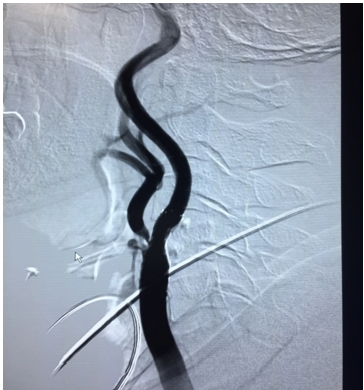

患者,沈某,67岁,男性,长期头痛、头晕,发作性眼前黑朦、言语不利,右侧肢体发麻、无力症状,曾在省内多家医院求诊,均以“脑供血不足”给于药物治疗,未规范筛查血管,症状仍反复发作。此次就诊于我院心脏介入科,行颈部血管彩超提示:左侧颈内动脉、左侧锁骨下动脉重度狭窄,左侧锁骨下动脉盗血症。双上肢血压监测提示:左侧血压较右侧明显偏低(双侧动脉压差>30mmHg),头颅磁共振:颅内未见梗死灶。心脏介入科医师请神经外科会诊后行全脑血管造影术检查,提示:左侧颈内动脉起始端狭窄,狭窄率62.6%。左侧锁骨下动脉椎动脉近心端狭窄,狭窄率73.6%,左椎动脉正向血流未显影,右椎动脉反向左椎动脉供血。

经过术前准备,医院为患者实施同期“左侧颈内动脉、锁骨下动脉狭窄自膨胀支架置入术”,手术在局麻下进行,用时70分钟圆满完成。术后造影见支架贴壁良好,狭窄解除,左侧颈内动脉远端充盈良好,左椎动脉前向血流恢复,右椎动脉血流前向,返流消失。术后患者监测双侧上肢血压,脉压差介于10mmHg之间,患者头痛、头晕及肢体无力症状较前明显改善。术后3天复查颈部血管彩超,血运明显改善。患者未出现任何并发症。